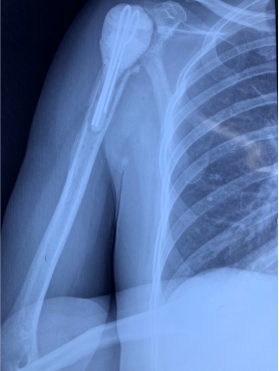

术前影像

齐齐哈尔市的李女士,7个月前务农时不幸被机器绞伤右侧肩膀,导致肱骨近端骨折,在当地医院做切开复位、内固定手术,术后发生感染。患者辗转多家医院都没有治愈,遂找到王文波求治。